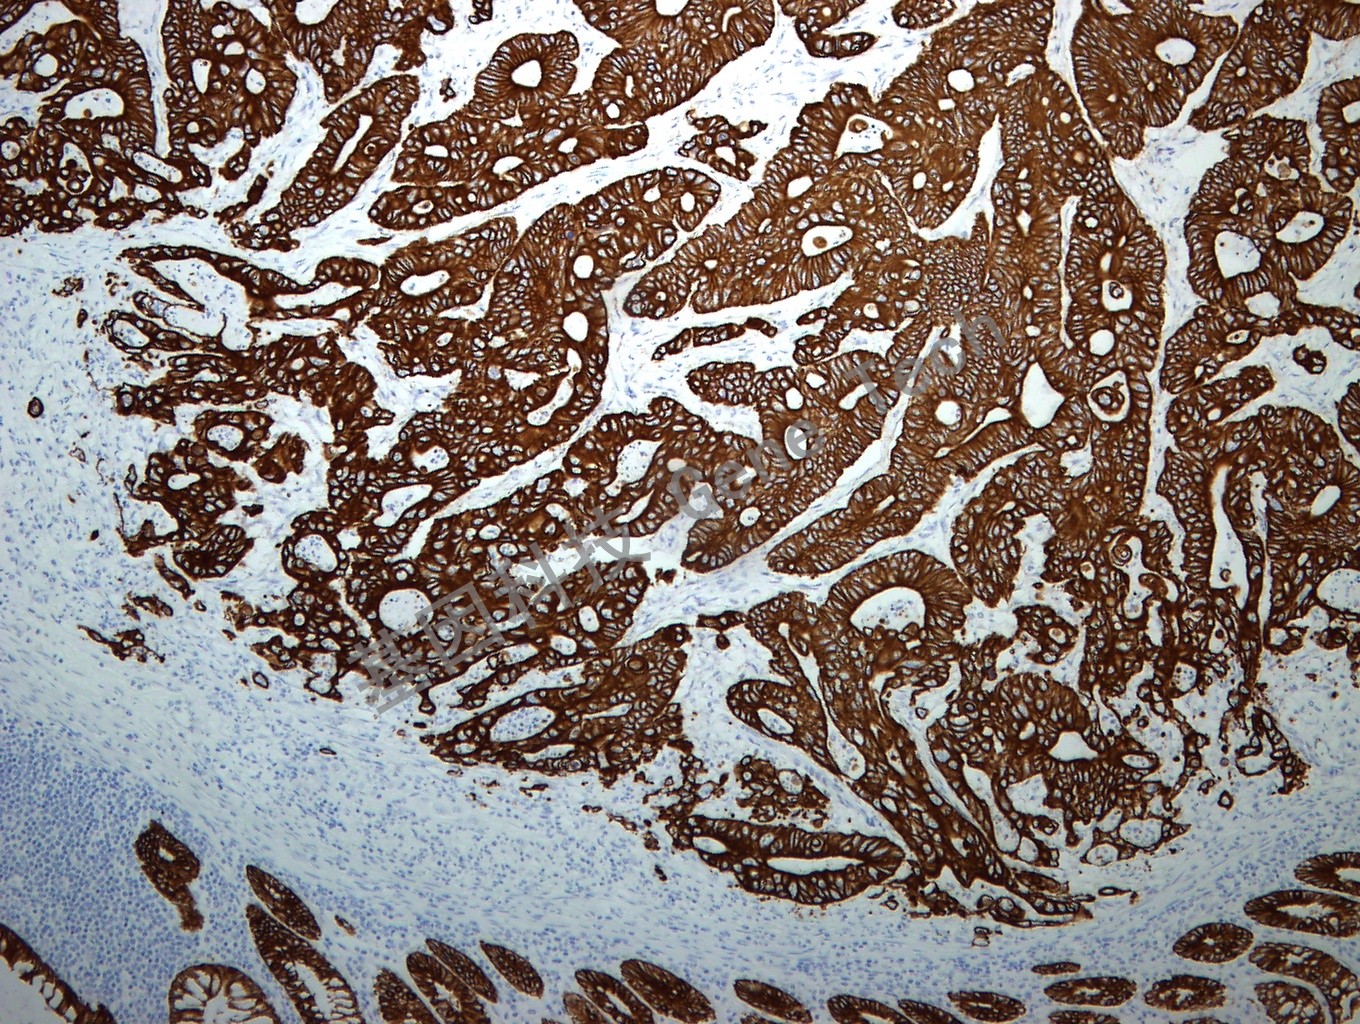

Milk Fat Globule1 鼠抗人 乳脂肪球膜蛋白1(HMFG1)

克隆號:EDM45 陽性對照:乳腺癌 陽性部位:胞膜/胞漿

預(yù)處理:高pH 熱修復(fù) 適用:石蠟切片/冰凍切片 顯色系統(tǒng):GTvisionTM

簡介:HMFG1 位于人乳脂肪球外表面,存在于正常人乳腺上皮細胞和源于乳腺癌的細胞系。HMFG1 被認為是一種分化標記,可以作為正常乳腺和乳腺腫瘤發(fā)育的特異性上皮標記。HMFG 實際為EMA(又稱MUC1、CD227),本克隆是一個很好的EMA 檢測工具。